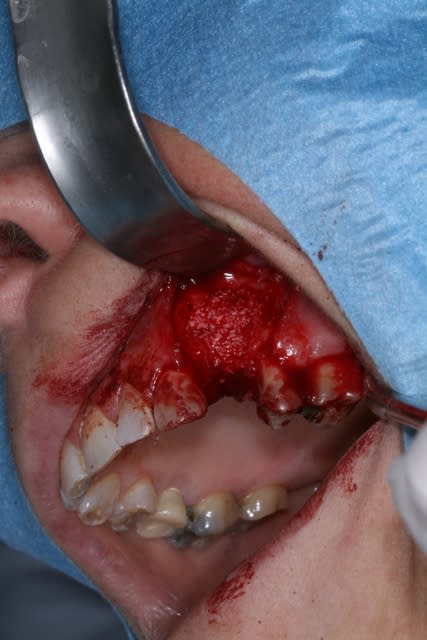

un cas dont j'avais discuté ailleurs avec amibien qui m'avait reproché de ne pas avoir fait la pose en même temps en juin dernier

la pose est de jeudi dernier mon apn est en panne, photo avec le portable, desolé pour le sang mais quand cela saigne il n'y a pas d'échec

il se trouve que j'aimerais utiliser ces photos car c'est le nouveau systeme d'implants, et je n'ai encore pas d'autres cas de fracture en cours

j'ai donc agrandi la zone est ce qu'un pro de la photo peut faire mieux?

pour dudule, je ne fais pratiquement jamais de décharge en distal